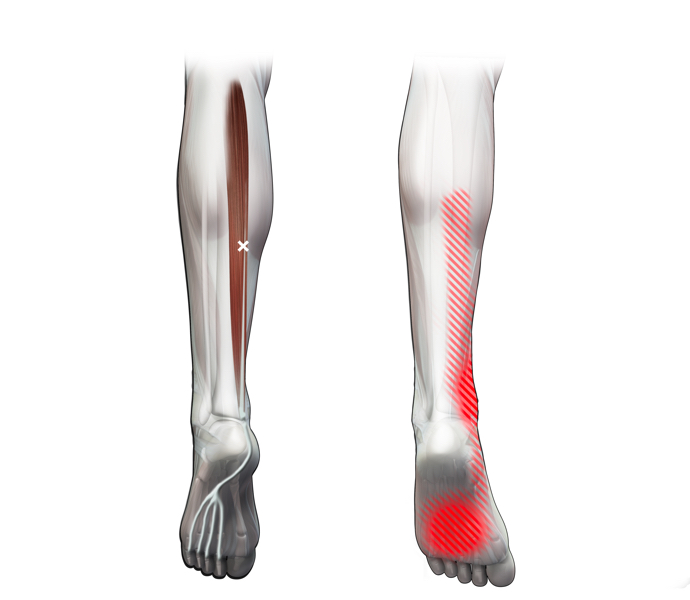

Spieren (Nederlands)

Spieren (nederlands)

Spieren (Latijn)

Spieren (latijn)

Trefwoorden

Trefwoorden